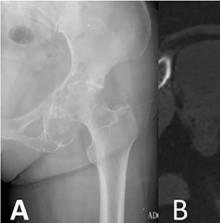

📷 Radiografía

La radiografía suele mostrar matriz condroide calcificada, con patrón en anillos y arcos, junto con scalloping endostal y posible expansión cortical.

Figura 1. Radiografía de condrosarcoma con matriz condroide calcificada.

🖥️ Tomografía computarizada (TC)

La TC define mejor la mineralización condroide y la integridad cortical, y es especialmente útil en pelvis, costillas, escápula y otras localizaciones complejas.

Figura 2. TC de condrosarcoma con mejor definición de la mineralización y la cortical.